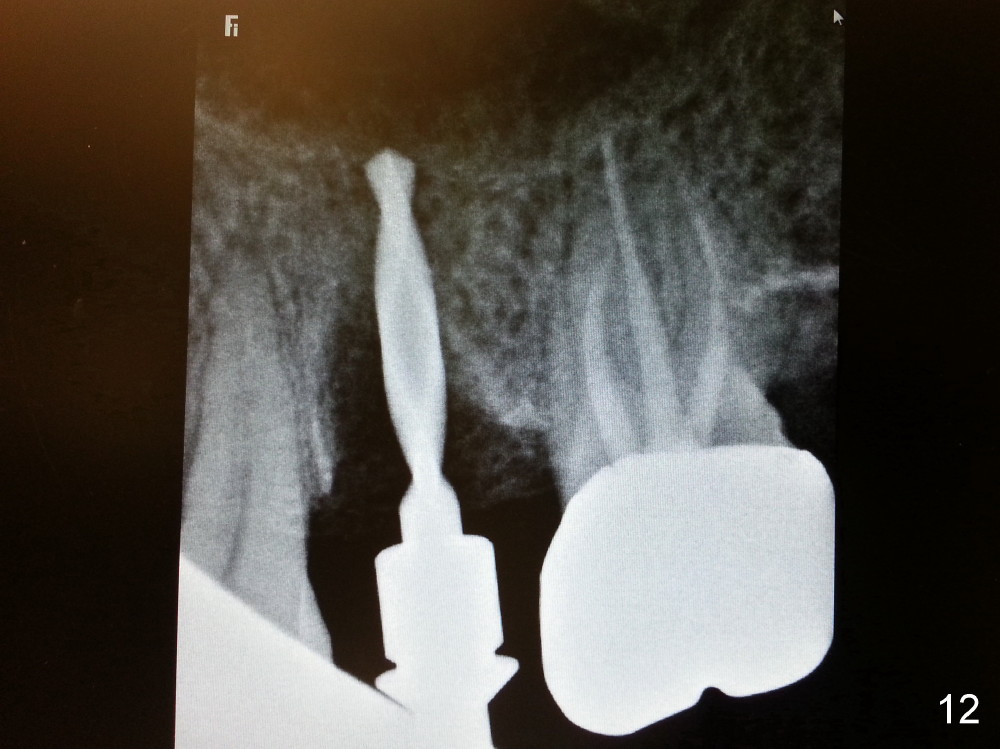

Grafting Following Immediate Implant (Photos Provided by Xue Steven, DDS)

The tooth #13 appears to be affected by periodontits and occlusal trauma (Fig.1*). After using a periotome (Fig.2), the tooth is extracted (Fig.3). The buccal flap is raised (Fig.4). Gingival graft is to be harvested from the site of #15 (Fig.5). The tissue is elevated buccally (Fig.6) and separated (Fig.7). The donor site is covered by a collagen membrane (Fig.8*). A diamond bur is used to induce bleeding from the socket (Fig.9*). Osteotomy is initiated (Fig.10) and enlarged (Fig.11,12). A tapered implant is being placed (Fig.13-15) following internal sinus lift (Fig.16,17). The implant is placed subcrestally, followed by bone graft (Fig.18), soft tissue graft (Fig.19), and suturing (Fig.20 <, Fig.21).